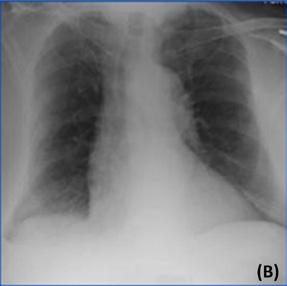

Rapport de radiologie généré par ChatGPT :

Deux radiographies de poumons de face pour contrôle. Celle qui est réalisée récemment (B) montre une amélioration significative de l’état du patient par rapport à la radiographie précédente (A). L’analyse précédente a montré un épanchement pleural, qui est une accumulation de liquide dans l’espace entre les poumons et la paroi thoracique. L’analyse actuelle montre que l’épanchement pleural a disparu. Il n’y a aucune preuve de nouvelles anomalies dans les poumons ou la paroi thoracique. Les poumons semblent bien dilatés et la taille du cœur est normale. Le médiastin, qui est l’espace entre les poumons, se situe également dans les limites normales.

■ Conclusion : L’état du patient s’est amélioré depuis la dernière radiographie thoracique, avec résolution de l’épanchement pleural précédemment constaté. Aucune nouvelle anomalie n’est observée.

■ Avis des radiologistes : Amélioration de l’épanchement pleural.